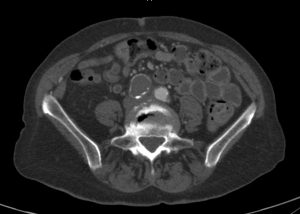

Renal Infarction

When the kidney, or part of it, does not receive blood, this may cause a renal infarction. Sometimes, blood flow is limited because of a local problem. But often, systemic illness is the problem. Symptoms of Renal Infarction Renal infarction is often diagnosed late. The reason is that symptoms are non-specific. Patients often have abdominal…